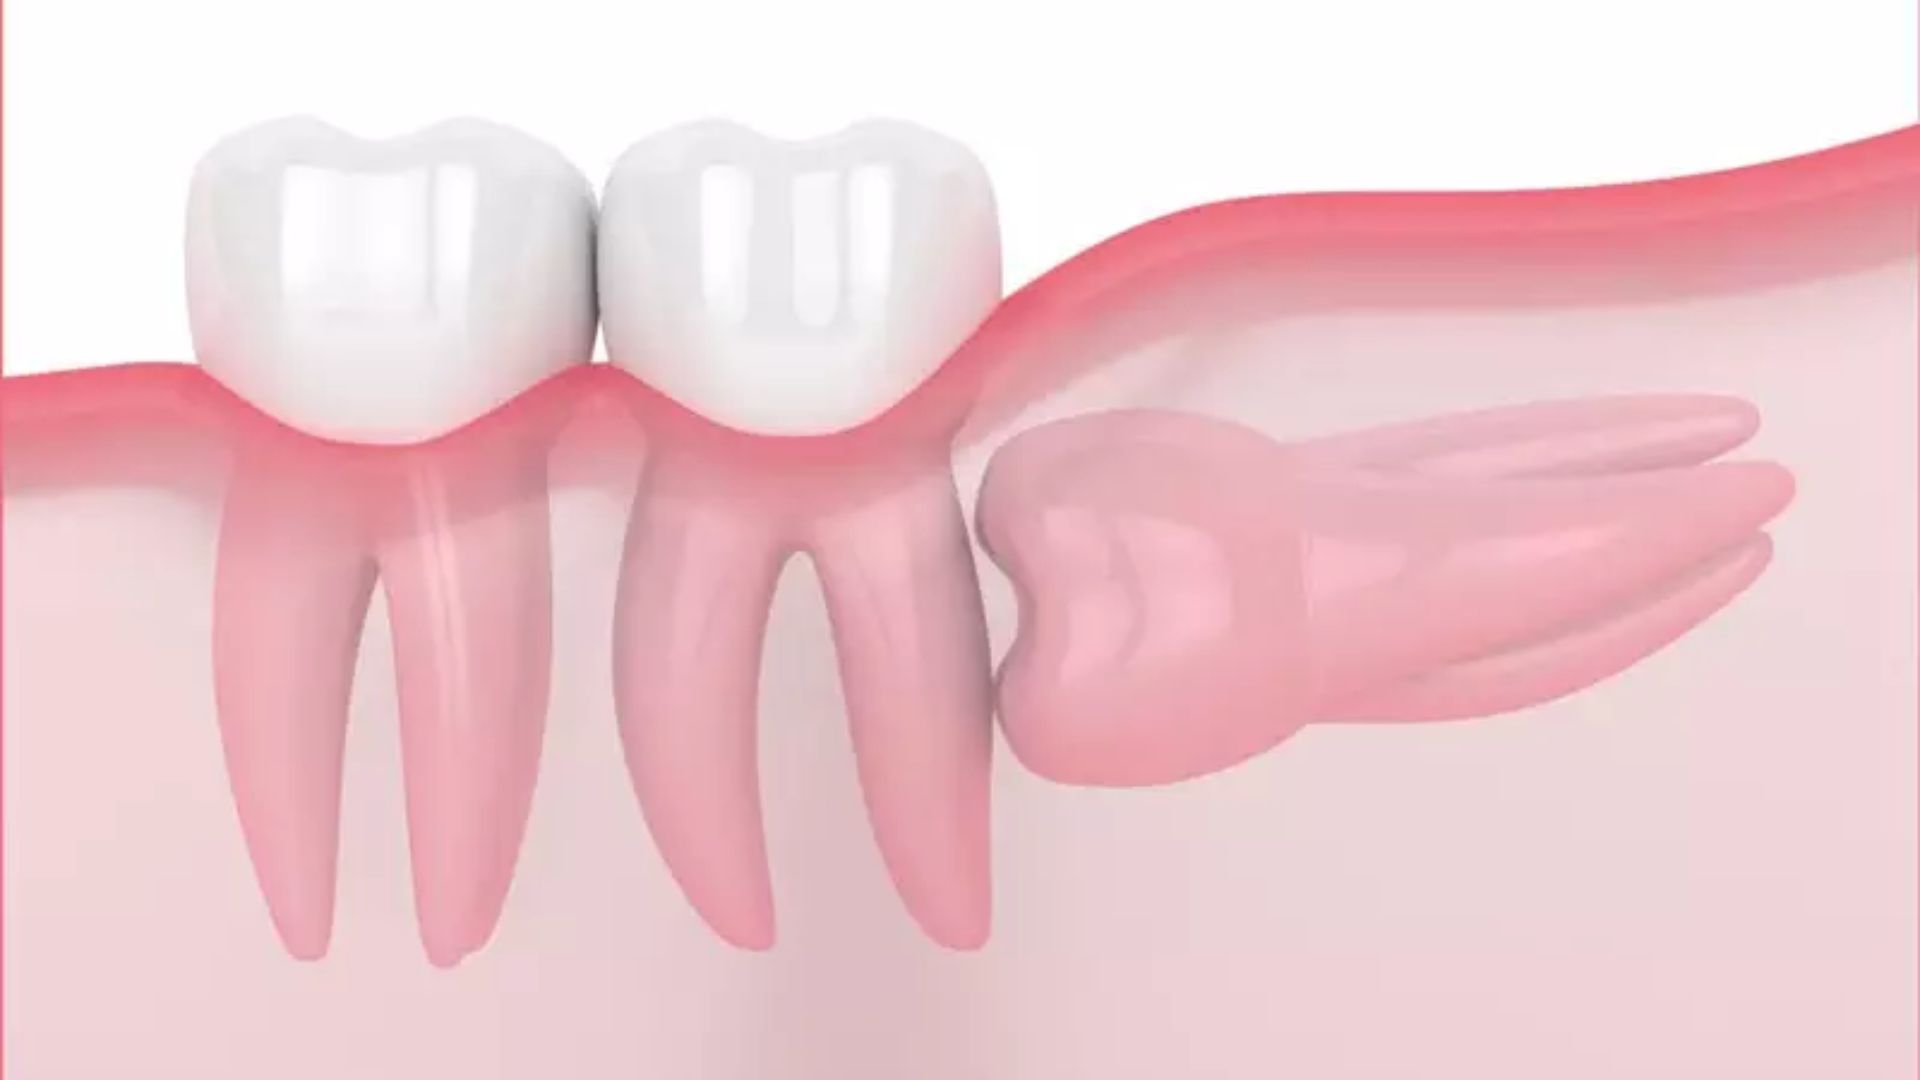

Răng khôn là những chiếc răng mọc phía trong cùng hai hàm răng, trường hợp xương hàm của chúng ta đã ngừng phát triển. Răng khôn thường mọc từ giai đoạn tuổi 17 đến 25, dù vậy cũng có một số trường hợp răng khôn mọc ngoài giai đoạn này. Sẽ có tổng cộng 4 chiếc răng khôn ở mỗi người chúng ta ở cả 2 hàm.

Vì răng khôn mọc khá sát vách và trong cùng một hàm dễ dẫn đến tình trạng mọc đâm xiên, mọc lệch vào răng bên cạnh dẫn đến hiện tượng sưng lợi, đau răng, nhiễm trùng vùng nướu xung quanh. Bên cạnh đó, răng khôn thường sẽ được nhổ bỏ vì thực tế chẳng có công dụng gì nỗi bật.